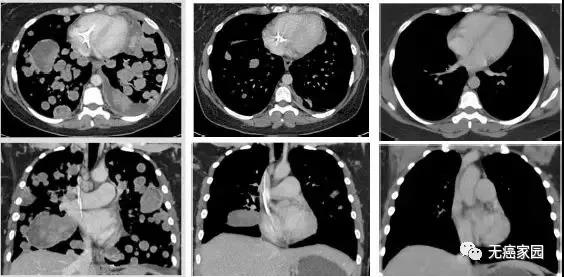

现在,她的随访扫描结果显示,在过去三年她都已经没有癌症的迹象!

图示分别为治疗前、治疗3周期第1天、治疗13周期第1天